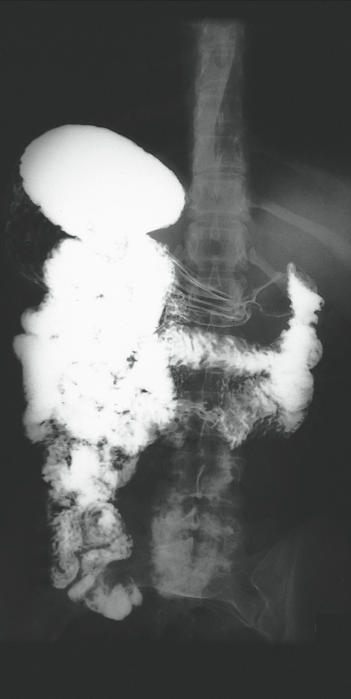

A 30-year-old woman had had no medical problems until she suffered a 4-week bout of coughing, wheezing, and fever while traveling in Indonesia. This was followed by diarrhea, nausea, vomiting, abdominal pain in the right upper quadrant, and anorexia. She returned to the United States, and her symptoms partially subsided. She sought no medical care at that time.

During a trip to Japan 3 years later, she had occasional attacks of diarrhea that contained bright red blood. This was attributed to external hemorrhoids. Returning to the United States about a year later, she continued to experience abdominal pain, nausea, and diarrhea. The following year, the diarrhea, nausea, and vomiting increased, and she lost weight. The diarrhea was worse at night, often awakening her.

The patient finally consulted a gastroenterologist 6 months later. Results of stool studies were negative for organisms, and findings from flexible sigmoidoscopy were within normal limits. Biopsy of the colonic mucosa revealed lymphoid aggregates. A subsequent upper GI series showed multiple ascarides in her stomach, duodenum, and small intestine. Within days, an esophagogastroduodenoscopy was performed but revealed no evidence of ascarides. The patient was treated with pyrantel pamoate, and her symptoms finally resolved.

Ascaris lumbricoides is harbored by 25% of the world population, including 4 million Americans. It is the largest nematode (15- to 45-cm long) that infects humans and is found predominantly in the jejunum, maintaining its position there with its intense muscular activity.

The typical A lumbricoides lives for 1 year, and each adult female produces about 200,000 eggs daily. Following fertilization, the eggs develop in moist soil before being ingested by the human host. The life cycle of these worms involves a 2-step process: an early, extraintestinal pulmonary phase followed by a prolonged intestinal phase. They hatch in the small intestine, then migrate through the intestinal wall and travel to the lungs via the bloodstream or lymphatics. About 10 days later, they ascend the tracheobronchial tree, are swallowed, and return to the small intestine to complete their maturation 14 days later.

A lumbricoides does not manifest itself clinically, but 3 clinical syndromes can occur. The pulmonary phase (4 to 16 days after ingestion) involves cough, fever, wheezing, dyspnea, and angioedema or urticaria. In the GI phase, patients have vague abdominal discomfort, colic, and occasional diarrhea. Complications of ascariasis include intestinal obstruction, usually in the ileum; not uncommonly, the worms migrate into the biliary ducts, producing a picture of acute cholangitis or hemorrhagic pancreatitis. Less frequent complications include appendicitis, intestinal perforation, peritonitis, liver abscess, and obstruction of the upper respiratory tract.

The diagnosis of A lumbricoides infection is usually made by demonstrating embryonated and unembryonated eggs and adult worms in the feces, although this patient’s stool studies were negative. In addition, an upper GI series with small bowel follow-up can be diagnostic—as it was in this case. After the patient’s bowel is emptied of barium, A lumbricoides may be identified by its barium-filled intestinal tract.

All patients who acquire worms need to be treated because of the danger of complications. Give pyrantel or mebendazole; piperazine is an inexpensive alternative. Do not use mebendazole or piperazine in pregnant women.

(Case and photographs courtesy of Drs Armand Cacciarelli, James Robilotti, and Emma Bell.)